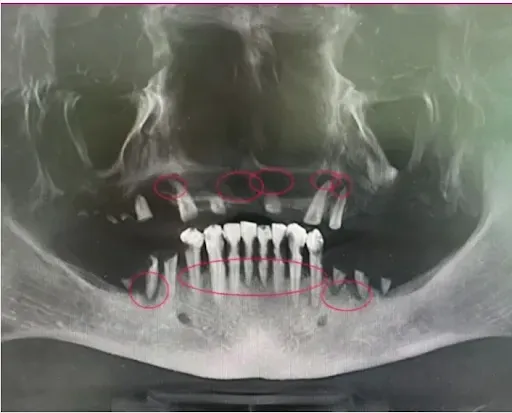

The scan below makes it easy to see how missing just one or two teeth in one part of the mouth causes significant bone loss. Look at the upper right side in the picture below. Can you see the larger curve upward? That is how much bone had disappeared because there was no tooth OR dental implant there to keep the bone stimulated.

Likewise, on the bottom left side, you can see a large downward curve because the back molars had been missing for quite some time. The longer these issues go uncorrected the more dangerous and expensive the corrections become.